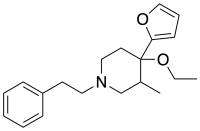

Indoles

- 18-Methoxycoronaridine

- 7-Acetoxymitragynine

- 7-Hydroxymitragynine

- ψ-Akuammigine

- Akuammidine

- Akuammine

- Coronaridine

- Eseroline

- Hodgkinsine

- Ibogaine

- Mitragynine

- Mitragynine pseudoindoxyl

- Noribogaine

- Pericine

- Pseudoakuammigine

Structures

| Indoles | ||||

|---|---|---|---|---|

|

7-Acetoxymitragynine |

|

Akuammidine |

|

|

|

-Mitragynine_Structural_Formula_V1.svg.png.webp)

|

|

|